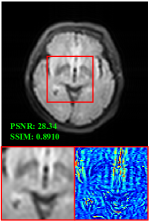

Figure 5 provides the qualitative comparison of the various methods on the four datasets at a scale of 4. The top, second, third, and bottom rows are the SR results under the FastMRI, clinical brain, clinical tumor and clinical pelvic datasets, respectively. The red boxes indicate the zoom-in region of complicated anatomical structures along with their corresponding error maps. Note that the brighter textures in the error maps, the lower the quality of the reconstructed images. As can be seen, compared to methods based on Transformers and CNNs, diffusion-based methods like DisC-Diff and DiffMSR (Ours) are capable of reconstructing high-realistic images with promising reconstruction metric scores (PSNR and SSIM). Nevertheless, while DisC-Diff can reconstruct high-precision MR images, it does not preserve the structure present in the original HR images, introducing some additional information that can affect medical diagnosis. In contrast, our method combines DM and PLWformer, which can preserve the original image’s structure while restoring high-frequency information.

In this section, we present more visual qualitative comparisons. Figures 8, 9, 10, and 11 show the reconstruction results of each method in FastMRI, clinical brain, clinical tumor, and clinical pelvic, respectively. As can be seen, although DisC-Diff can reconstruct MR images with high-frequency information, it fails to preserve the structure and content of the original Target HR image effectively, resulting in image distortion. In contrast, our proposed DiffMSR can restore high-frequency information while preserving the structure of the original HR image, indicating the effectiveness of the joint use of DM and PLWformer.